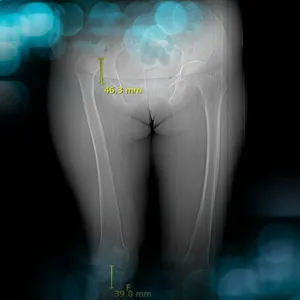

The goals of this clinical case are to discuss the classifications and therapeutic options for a hip dysplasia in a middle aged patient